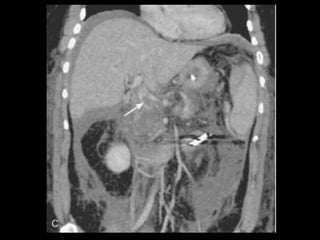

PANCREATITE AGUDA GRAVE

A administração de contraste IV é essencial,

especialmente em pacientes com PA grave, para

visualizar o pâncreas, diferenciar a glândula de

coleções líquidas adjacentes e do tecido

inflamatório peripancreático e demonstrar a

necrose pancreática.

Áreas focais ou difusas de realce diminuídas ou

ausente à TC contrastada dinâmica constituem

áreas de isquemia ou necrose.

TC tem precisão geral de 87% com S e E de 100%

para necrose extensa e 50% com áreas menores.